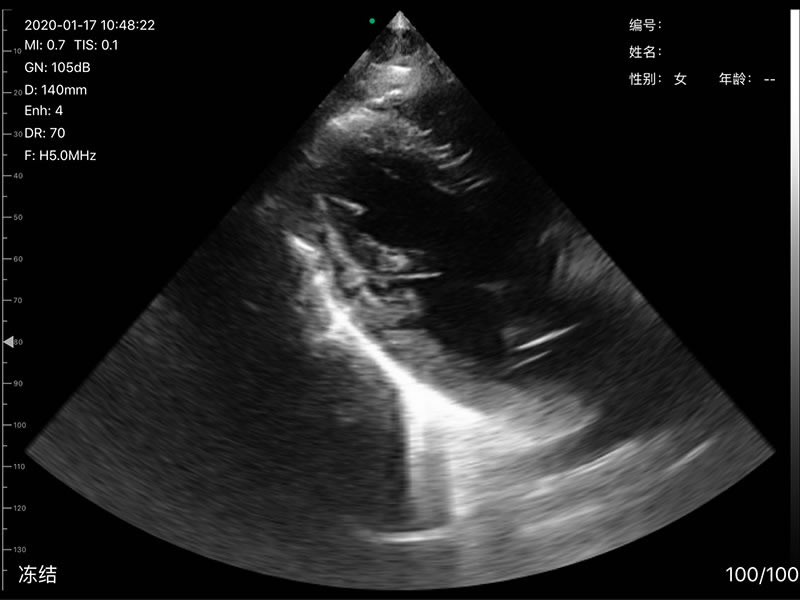

• 探头频率:相控阵2.2/3.6MHz,线阵7.5/10 MHz

• 扫描深度:相控阵20-240mm,线阵 20-100mm,可调

• 扫描角度和宽度:相控阵80mm,线阵25mm